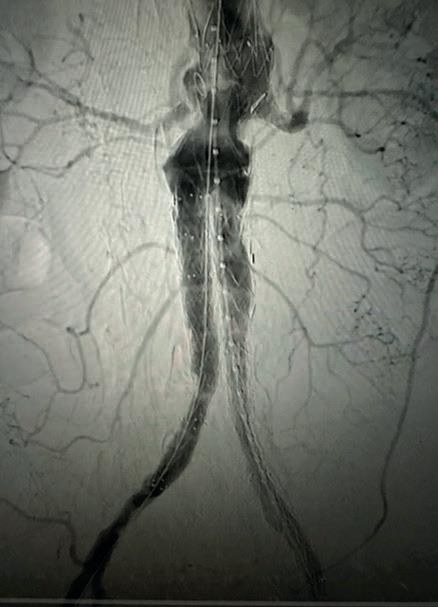

Significant life and limb gains for claudicants who stop smoking before lowerextremity bypass

LONG-TERM OVERALL survival (OS) and amputation-free survival (AFS) are outcomes that rebound in claudicants who quit smoking prior to elective surgery—and they mirror those of never smokers. But patients who do not kick the habit have significantly worse outcomes, lighting up the question: should stubbing out for good be “a requirement” before intervention?

That was the message from Rohini J Patel (University of California San Diego, San Diego, USA), who presented data at this year’s Society for Vascular Surgery (SVS) Vascular Annual Meeting (VAM 2023; 14–17 June, National Harbor, USA) on long-term outcomes in the smoking claudicant after elective lower extremity bypass. The findings were published simultaneously in the Journal of Vascular Surgery (JVS).

Patel noted that patients and vascular specialists must grasp that structured smoking cessation should be a more

prominent part of vascular office visits before and after lower extremity bypass and can “even be considered a requirement prior to elective procedures in claudicants”, a group that represents a unique non-emergent vascular patient population that can require lower extremity bypass.

Smoking is known to increase complications, including poor wound healing and coagulation abnormalities, and have cardiac and pulmonary ramifications, said Patel. “Across specialties, elective surgical procedures are commonly denied to active smokers. Given the base population of active smokers with vascular disease, smoking cessation is encouraged but is not required the way it is in general surgery,” she explained.

The research team queried the Vascular Quality Initiative Vascular

Implant Surveillance and Interventional Outcomes Network (VISION) database

over a 16-year period to tackle the question of how actively smoking claudicants fare after elective lower extremity bypass. They then carried out two separate propensity score matches on patient records that included 609 (10%) never smokers, 3,388 (55.3%) former smokers, and 2,123 (34.7%) current smokers who underwent bypass for claudication. One analysis examined the outcomes of former smokers and compared these to outcomes achieved in patients who had never smoked. The second analysis contrasted outcomes between current smokers and former smokers. The primary outcome measures included five-year OS, limb salvage (LS), freedom from target lesion reintervention (FTR) and AFS.

Health gains do not shift unless claudicants quit smoking

There were no differences recorded with respect to any of these measures between 497 well-matched pairs of former smokers and those who had never smoked. The second analysis, which focused on ascertaining outcome differences between 1,451 wellmatched pairs of current and former smokers, found that there was no

difference in LS or FTR, but revealed “a significant increase in OS and AFS” in former smokers compared with current smokers, suggesting that giving up smoking reaps rewards in terms of both limb and life preservation.

“Our study found that former smokers have better OS and AFS when compared to current smokers, while former smokers mimic never smokers at five-year outcomes for OS, LS, FTR and AFS,” Patel averred.

Patel states: “This study emphasises that we as providers must spend more time and effort working with patients to quit smoking prior to elective lower extremity bypass in claudicants.”

Limitations of the study include that the database contained no information on the duration or intensity of smoking among the study population.

According to senior author Mahmoud Malas (University of California San Diego): “Previous studies have shown that smoking cessation might not necessarily affect an immediate outcome in patients. We have found through this VISION database that even quitting one month prior to surgical intervention can change longterm outcomes.

“Former smokers do better than current smokers and former smokers mimic the results of patients who have never smoked. As vascular surgeons, we need to play a more active role in these discussions with patients in the clinic.”